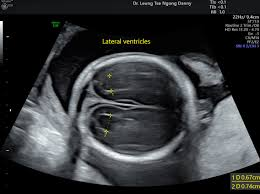

Brain ventriculomegaly, often diagnosed using ultrasound imaging, is a condition where the brain ventricles are abnormally enlarged. Like a protective helmet, the brain produces and circulates a protective fluid known as cerebrospinal fluid in spaces within the brain called ventricles. Some developing fetuses are diagnosed with ventriculomegaly due to changes to the lateral ventricles. It is detected during a mid-trimester ultrasound anomaly screening.

During the examination, the fetal medicine practitioner is required to measure the lateral ventricles size. Ventriculomegaly is diagnosed if the measurement of the lateral ventricles is above 10mm. Depending on the fetus’s condition, the diagnosis can be classified as:

01. Detailed fetal neurosonography – A specialised ultrasound to assess the fetal brain’s structure and any anomalies.